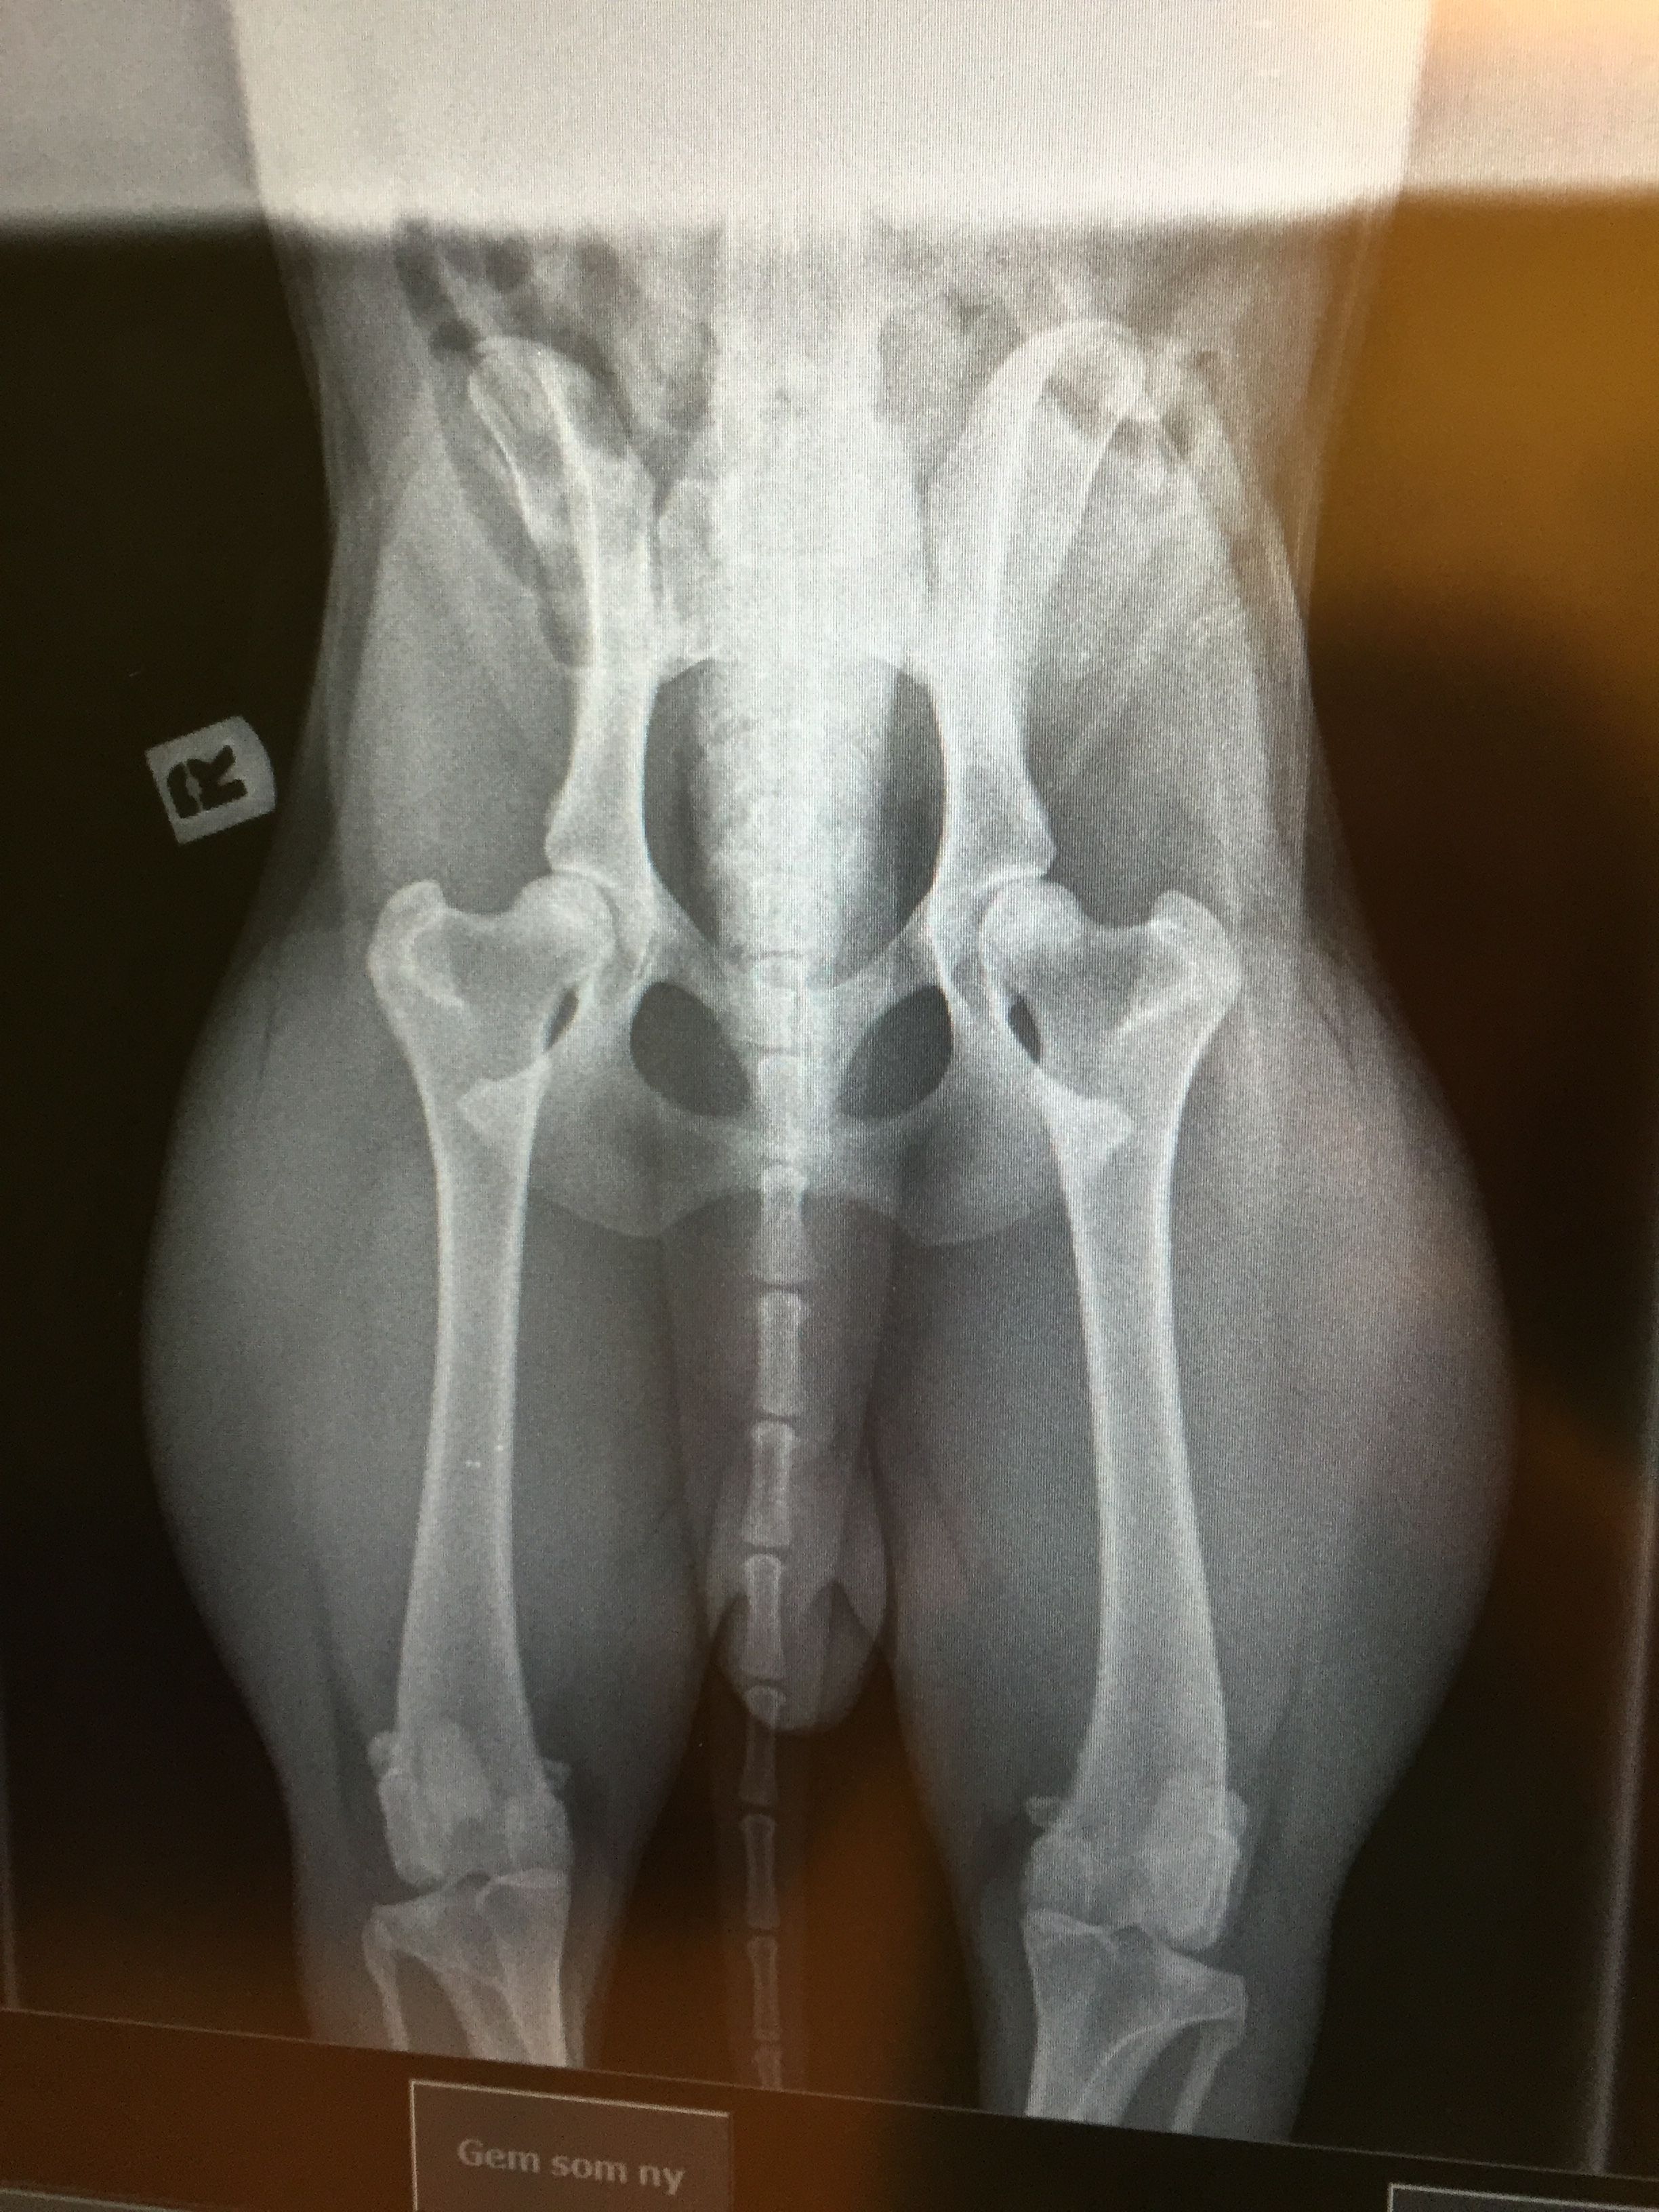

Hunden bedøves let, og der tages i alt 3 billeder af dens hofteled:

Et standard HD-billede som ovenfor beskrevet, et kompressions-billede hvor hofteleddet trykkes sammen, samt et distraktions-billede, hvor hofteleddet udsættes for et let press.

Udfra denne såkaldte stressoptagelse af leddene kan man måle, hvor stor hundens sandsynlighed er for at udvikle slidgigt i hofterne på et senere tidspunkt.

Metoden, som er ganske ufarlig for hundens hofteled, kan udføres fra hvalpen er fire måneder gammel.